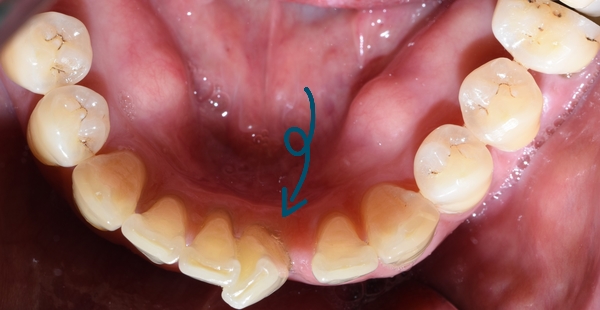

환자분은 40대 남자분으로, 아래 앞니가 원래 안이랬는데 점점 벌어진다고 하셨습니다.

이렇게 앞니가 벌어지게 되면 입안 틈이 까맣게 보여서 미관상 좋지 않은 것이 사실입니다.

환자분의 앞니 교정전 치아 상태입니다.

[2019년10월의 사진입니다.]

어떤 치아가 문제인지 한눈에 보입니다.

치아가 틀어진 정도가 심해서 이런 치아는 일반 앞니 부분교정 보다

좀 더 심화적인 조치를 취해야 했습니다.